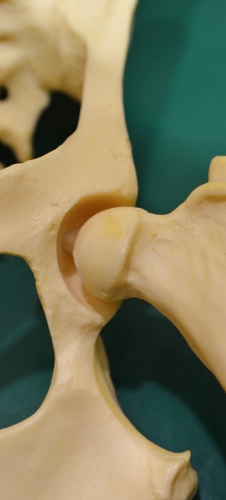

下の写真は股関節の重度の変形性関節症をしめす骨格モデルです。画面左の赤丸の中が重度に変形した関節構造をモデル化したものです。真ん中が正常な股関節で右がその部位の重度の変形関節症(拡大)です。